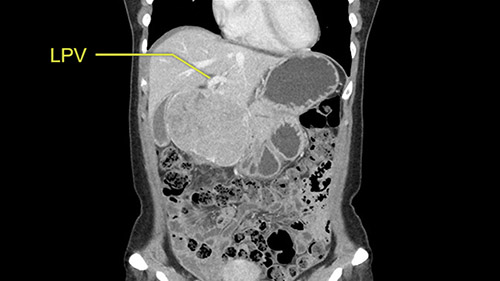

So if we look at the CT scan, on the axial, it’s a larger lesion. It’s about 6 or 7 or 8 centimeters. So it does look a bit threatening in terms of its resectability but if you really drill down deeply into the anatomy, and I think the coronal [imaging] is even better, you can see that the entire mass is on the patient’s left side of the falciform ligament. So it’s really only a left-sided tumor and not even really a left-sided tumor because Segment 4 is uninvolved anatomically.

As I review the CT scan, we have both arterial and venous phases, the tumor is obvious. But I’ll start by saying that the liver itself does not appear to be cirrhotic to my eye. It’s got a normal contour and allied to that, that I do not see evidence of portal hypertension. The spleen is normal, there’s no collateral vessels. The tumor itself, I measured maximally at about 11 centimetres in diameter and I’m told the alpha fetoprotein is very high (over 10000), which is entirely consistent with this being a solitary hepatocellular carcinoma that is very exophytic. It seems to emanate off the inferior margin of Segment 3 (because that’s the falciform). I’ll start by saying that this is not transplantable. The tumor exceeds our guidelines for transplantation, but it's likely resectable based on normal liver and no portal hypertension.

So the issue with regards to resection. A left sided tumor. I believe I can see the falciform ligament right here so we’re looking at a resection of Segments 2, 3 of the left lobe of the liver. The left portal vein is right there. I think we’ll be wiser to take the left portal vein and therefore get well into Segment 4 and do a left hemihepatectomy. Certainly, one does not need to take the middle hepatic vein; it’s miles from the tumor.

The other thing I would do in this case is to certainly to assess the coronal phase as we can see in the coronal phase, this tumor looks like it's growing from Segment 3, and again I don’t think there’s involvement of the right side of the liver or even on Segment 4.